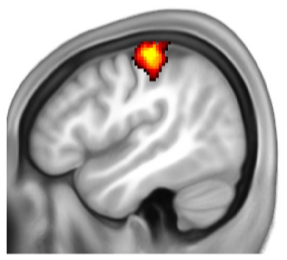

To explore this, 16 limb-different children and 16 limb-different adults took part in an fMRI neuroimaging study. We looked at how their brains responded when different body parts were touched, helping us to understand how the brain adapts to limb difference.

In limb-different participants, the area that typically supports hand function instead supported alternative body parts (e.g. arm, torso, feet).

The area that typically supports hand function instead supports alternative body part use. Stimulating the limb-different arm produced more activity than for the non-dominant arm of limb-typical children (difference shown as yellow/red spot).